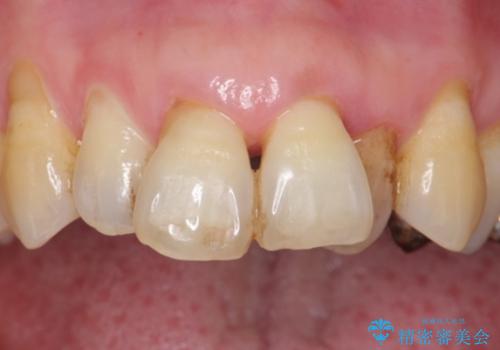

入れ歯も抵抗があるとのことから、相談を重ね、今の状態では保存不可能な下の前歯(左下2)を抜去し、ブリッジや連結補綴により動揺を抑えることにしました。

また、咬み合わせが反対になっている上の前歯(左上2)も補綴で形を変えることにより、咬合を改善しました。

- ¥1,110,000 (根管治療×1本、土台×2本、仮歯×9本、クラウン×9本)費用は治療当時の料金となります